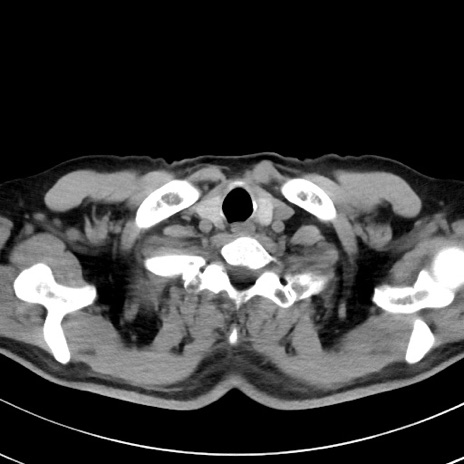

【腹部TIPS】症例29 参考症例 CT(横断像)

症例

70歳代男性